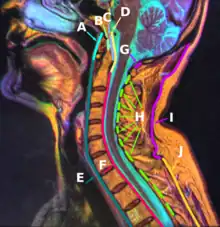

![]() Median sagittal section through the occipital bone and first three cervical vertebrae (ligament of apex dentis labeled at center left as apical odontoid ligament) | |

The ligament of apex dentis (or apical odontoid ligament) is a ligament that spans between the second cervical vertebra in the neck and the skull. It lies as a fibrous cord in the triangular interval between the alar ligaments, which extends from the tip of the odontoid process on the axis to the anterior margin of the foramen magnum, being intimately blended with the deep portion of the anterior atlantooccipital membrane and superior crus of the transverse ligament of the atlas.

B: Apical ligament of dens

It is regarded as a rudimentary intervertebral fibrocartilage, and in it traces of the notochord may persist.